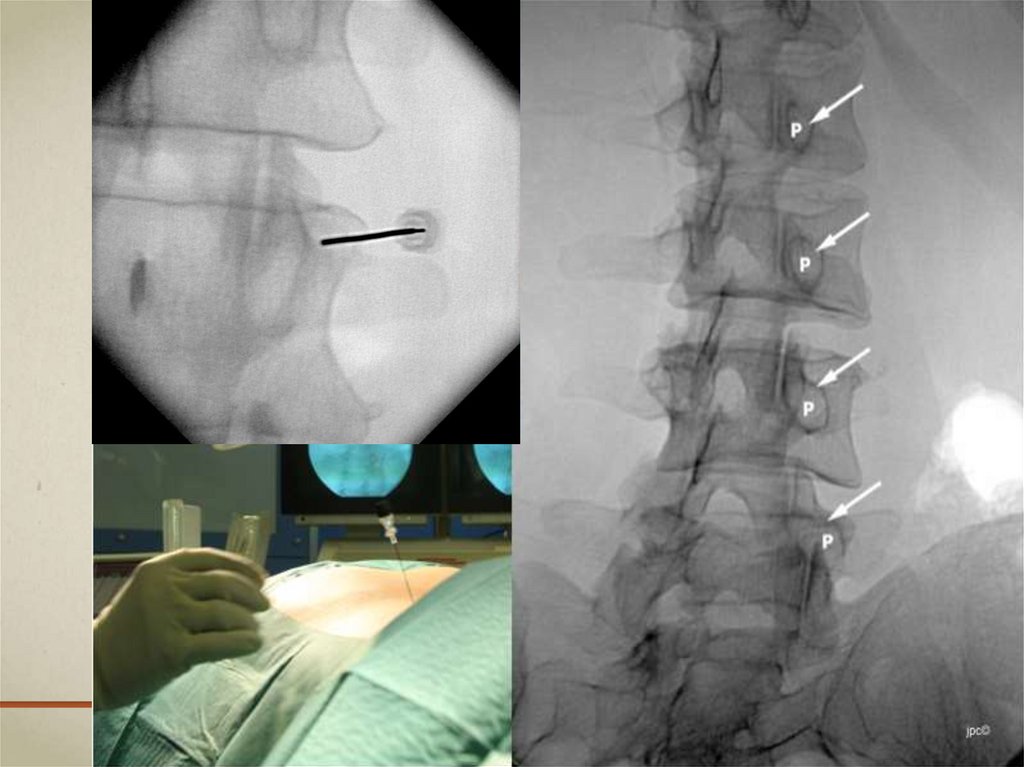

Артрогенная боль в поясничной области. Фасеточный болевой синдром. Интервенционные методы лечения

ОСНОВНЫЕ ИНТЕРВЕНЦИОННЫЕ МЕТОДИКИ

ИЗ АРСЕНАЛА КЛИНИКИ ЛЕЧЕНИЯ БОЛИ

• Тестовый блок

Диагностика генератора боли

• Лечебный блок

Лечебное воздействие на генератор боли,

диагностика